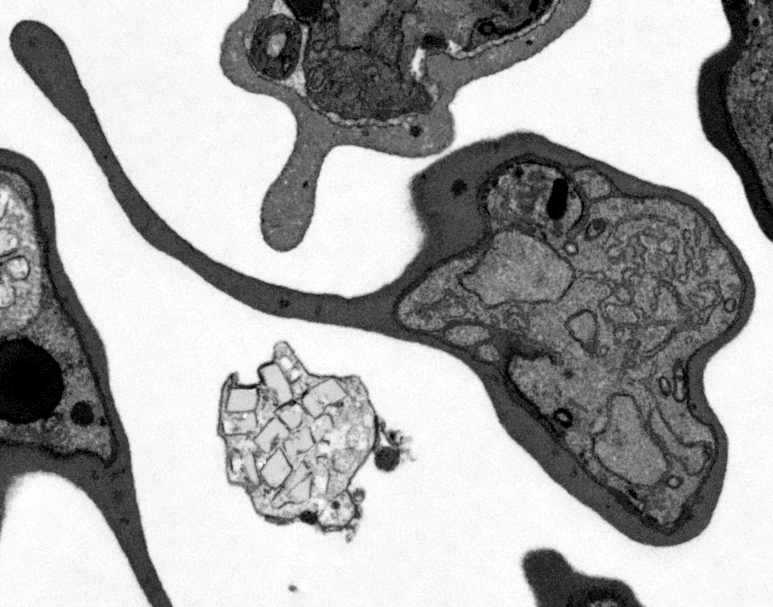

Actual z-index: 200Sampling: sampled from 397 source slicesScale: 10 x 10 x 20 nmContrast: per slice auto. Each generated plane is normalized independently for visual inspection.Frame cache: warming 0/96Keyboard: ←/→ step, Home/End jump.